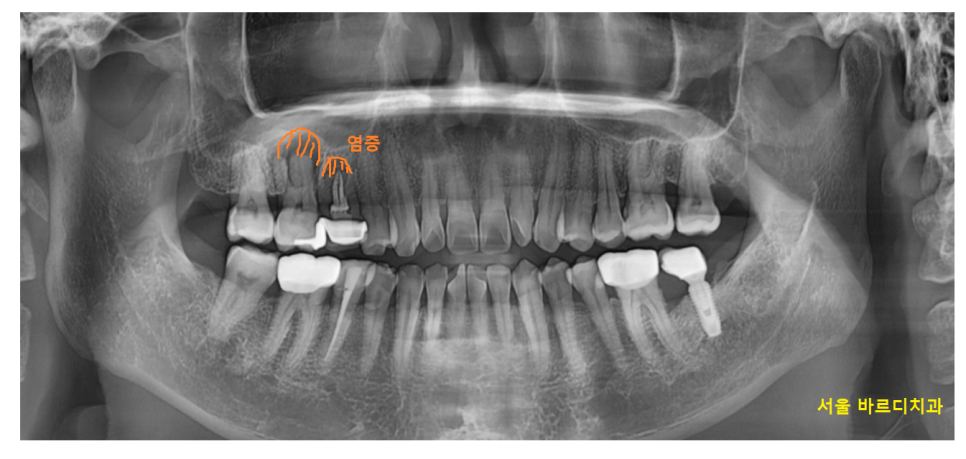

23.03.20

계속된 잇몸 뾰루지로

염증이 치아 주변 뼈를 녹였네요.

심지어 치아 뿌리가 일부 흡수된 모습까지 관찰